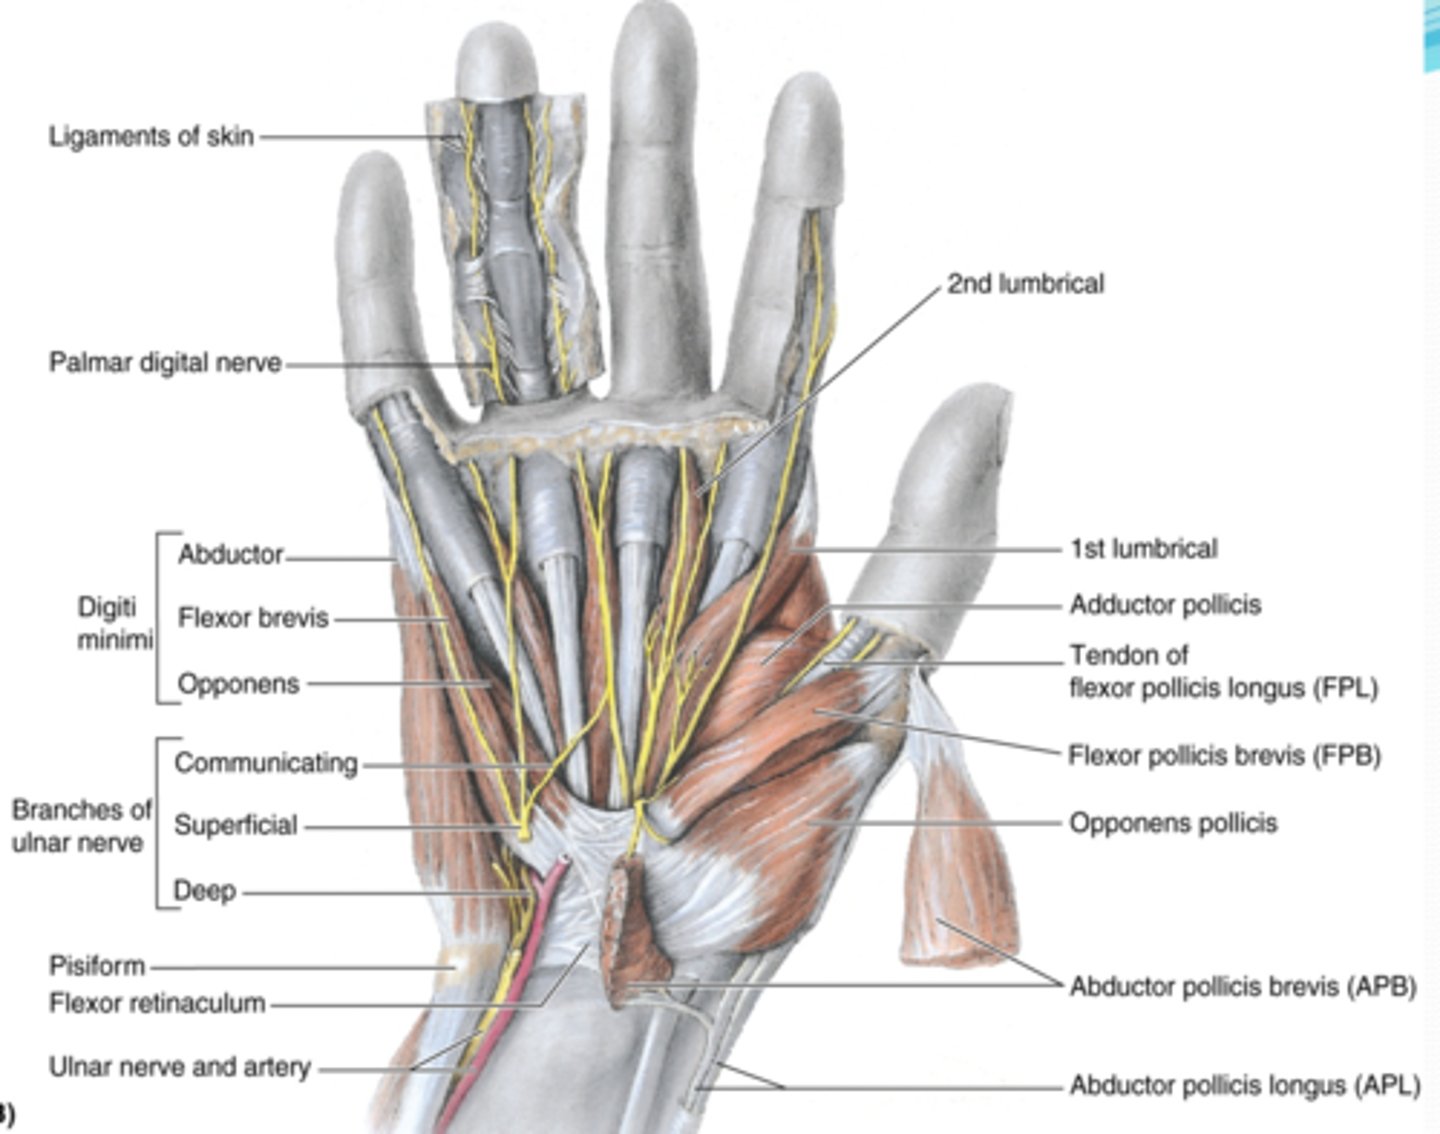

(Muscles of hand:) Muscles of thenar eminence

These muscles are responsible for opposition of thumb

-Abductor pollicis brevis (APB)

-Flexor pollicis brevis (FPB)

-Opponens pollicis

-Abductor digiti minimi

-Flexor digiti minimi

-Opponens digiti minimi

(Muscles of thenar eminence:) Abductor pollicis brevis (APB)

-Abducts 1st digit (thumb), helps opposition

-Median n. (C5 - T1)

-Forms anterolateral part of thenar eminence

(Muscles of thenar eminence:) Flexor pollicis brevis (FPB)

-Flexes 1st digit (thumb)

-Median n. (C5 - T1)

-Medial to APB

(Muscles of thenar eminence:) Opponens pollicis

-Opposes 1st digit (thumb)

-Median n. (C5 - T1)

-Deep to APB

(Muscles of thenar eminence:) Abductor digiti minimi

-Abducts 5th digit

-Ulnar n. (C7 - T1)

-Most superficial of the hypothenar muscles

(Muscles of thenar eminence:) Flexor digiti minimi

-Flexes 5th digit

-Ulnar n. (C7 - T1)

-Lateral to abductor digiti minimi

(Muscles of thenar eminence:) Opponens digiti minimi

-Rotates 5th digit bringing it into opposition with the thumb

-Ulnar n. (C7 - T1)

-Deep to abductor and flexor digiti minimi muscles

Short muscles of hand

lumbricals, dorsal interossei (4) , palmar interossei (3)

(Short muscles of hand:) Lumbricals

-Flex fingers at metacarpophalangeal joints and extend interphalangeal joints of 2nd - 5th digits

-Median n. (C5 - T1)

(Short muscles of hand:) Dorsal interossei (4)

-Abduct fingers

-Ulnar n. (C7 - T1)

-Between the metacarpal bones

(Short muscles of hand:) Palmar interossei (3)

-Adduct fingers

-Ulnar n. (C7 - T1)

-On the palmar surface of metacarpal